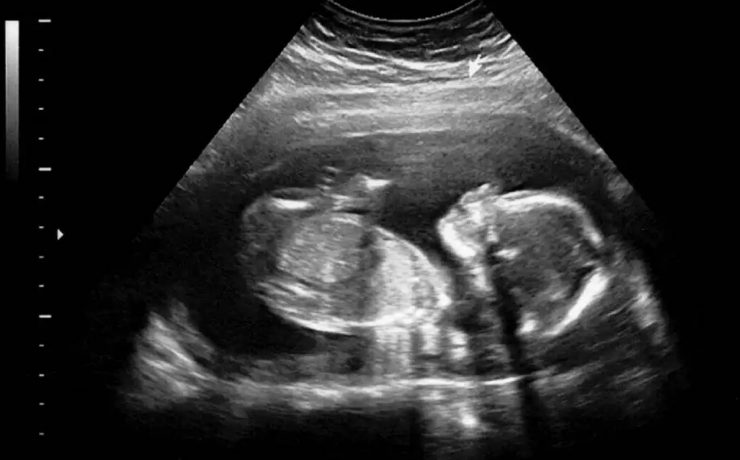

El síndrome de Rokitansky, es la anomalía más grave del tracto reproductivo femenino. Consiste en la ausencia congénita de vagina y útero ausente o rudimentario, como consecuencia de la falla en el desarrollo Mûlleriano de la vagina y el útero. Este síndrome fue descrito por Rokitansky en 1838. Es la